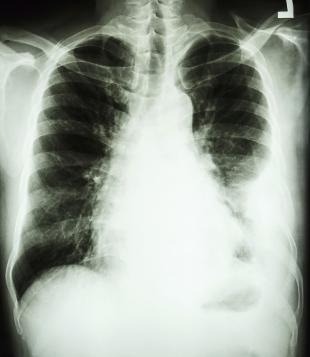

La dialisi polmonare è un sistema ideato e prodotto in Italia, che al pari della dialisi renale, permette di rimuovere parte dell'anidride carbonica dal sangue. Presso la Terapia intensiva universitaria dell'ospedale Molinette della Città della Salute e della Scienza di Torino, diretta dal professor Marco Ranieri, questo sistema mini-invasivo di rimozione dell'anidride carbonica è stato applicato con successo su 25 pazienti con grave riacutizzazione di broncopneumopatia cronica ostruttiva.

I ricercatori hanno dimostrato come l'applicazione dell'innovativa "dialisi polmonare", abbattendo i livelli di anidride carbonica nel sangue, abbia significativamente ridotto il rischio di intubazione, dal 33% al 12%, e le conseguenze negative che ne derivano, in pazienti con imminente fallimento della ventilazione non-invasiva.